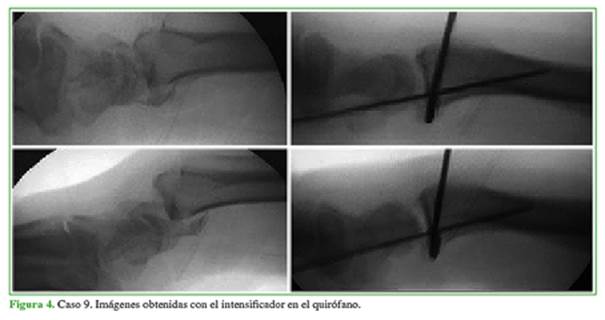

Con relación a la técnica quirúrgica, en su gran mayoría, este tipo de lesiones requiere de una osteosíntesis de la estiloides radial, reanclado de la cápsula articular y sutura ligamentaria (radiosemilunar corto). Se utilizó el abordaje de Henry para radio distal (Figura 3). No fueron necesarios abordajes dorsales debido a la correcta reducción indirecta de los fragmentos fracturarios. La estabilidad/reducción fue controlada mediante radioscopia dinámica en el quirófano (Figura 4).

3-11). Dada nuestra experiencia con el abordaje de Henry modificado para radio distal, se utilizó en ocho casos y no fue necesario un abordaje dorsal. En un paciente, la reducción cerrada fue aceptable y se decidió la fijación mediante tratamiento percutáneo.